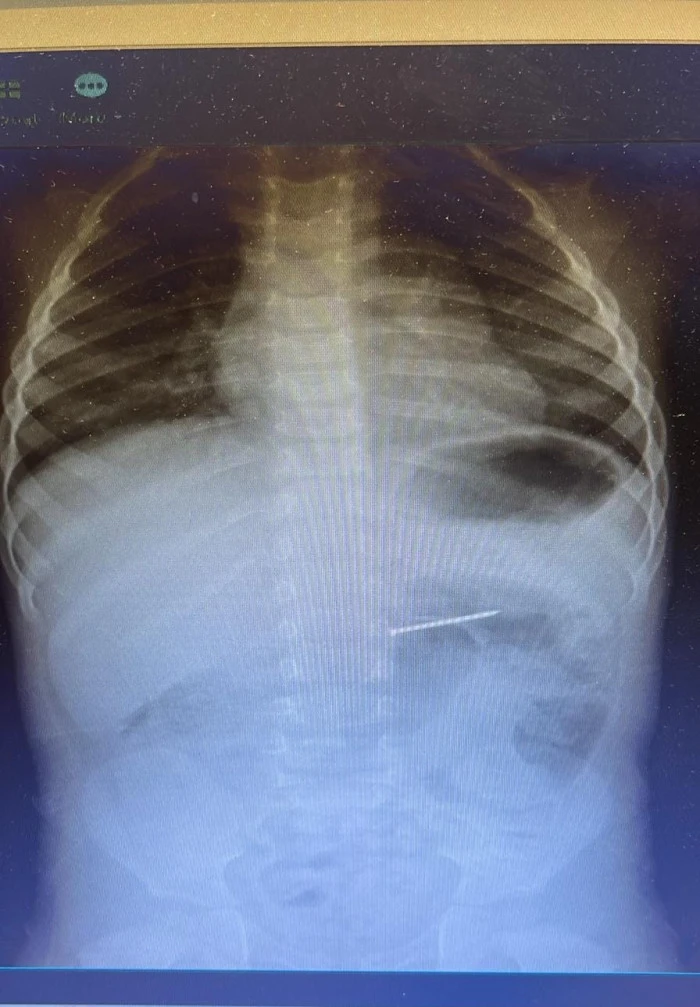

Küçük yaştaki çocukların meraklı davranışları nedeniyle sıkça karşılaşılan yabancı cisim yutma vakalarından biri geçtiğimiz günlerde hastanemizde başarılı bir müdahale ile sonuçlandı. Ailesinin çocuğun çivi yuttuğunu fark etmesi üzerine acil sağlık ekipleriyle hastanemize ulaştırılan 2 yaşındaki hasta, Çocuk Gastroenteroloji ve Endoskopi Birimi tarafından değerlendirildi. Yapılan radyolojik görüntüleme ile cismin midedeki yerleşimi saptandı ve endoskopik işlemle yaklaşık 4 cm uzunluğundaki çivi başarılı bir şekilde çıkarıldı.